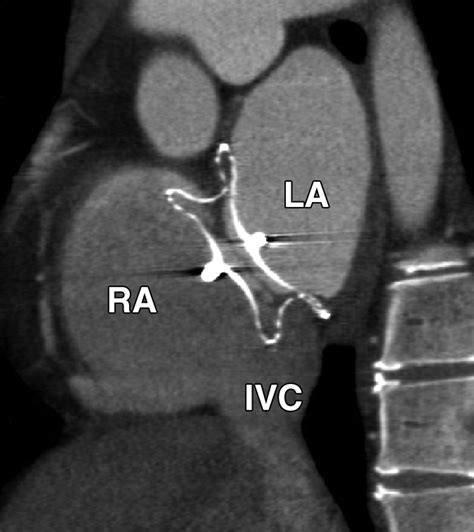

The Amplatzer Septal Occluder is specifically designed to address this by sealing the defect. It is essentially a self-expanding, double-disk device made from a flexible nitinol wire mesh. Once placed, it creates a "sandwich" effect that covers both sides of the hole, allowing the patient's own tissue to grow over the device over time, effectively healing the septal wall.

• Deployment: The Amplatzer Septal Occluder is pushed through the catheter. The left atrial disk is deployed first to anchor the device, followed by the right atrial disk.

Following the procedure, patients are usually prescribed a short course of antiplatelet medication, such as aspirin or clopidogrel, to prevent the formation of blood clots on the device while the body's natural tissue grows over it. Long-term follow-up is essential to monitor the closure success. Physicians typically schedule echocardiograms at the one-month, six-month, and one-year marks to ensure the Amplatzer Septal Occluder remains in the correct position and that there is no residual shunting of blood.